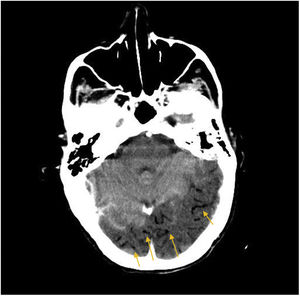

More infoA 72-year-old woman with chronic cough due to severe interstitial lung disease and fibrosis was found in a coma upon awakening. Glasgow Coma Scale score: 3. Gaze deviation to the left. Generalized hypotonia. Anisocoric pupils with right-sided mydriasis. Thoracic CT scan: small left apical pneumothorax and presence of ectopic air in the upper mediastinum (arrows) (Fig. 1). Brain CT scan: presence of numerous air bubbles located in the cerebral sulci (arrows), and cortico-subcortical hypodense areas distributed in bilateral parieto-occipital regions (Fig. 2). An intrapulmonary shunt would be mechanism involved that could explain our case (for the lack of a patent foramen ovale). A sudden increase of intrathoracic pressure due to Valsalva maneuvers, along with the development of pneumothorax and pneumomediastinum in a pathological lung could facilitate the passage of air into the pulmonary veins and from there into the left circulatory system causing cerebral air embolisms.